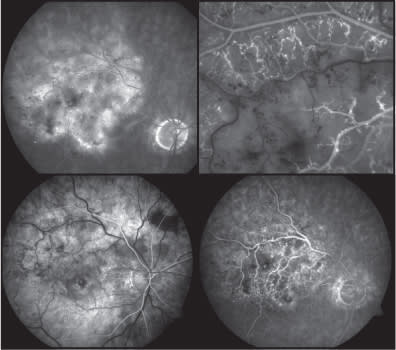

History and examination assist us in defining the “biological environment” within which a retinal occlusion (Figure 1) has developed. As always, the history can be modified to suit the patient. For example, in the younger person (under the age of 50), the inquiry focuses on aspects such as a family history of premature vascular disease. The use of certain drugs also needs to be specifically established. Notably, oral contraceptives and recreational agents (eg, cocaine) have been implicated in retinovascular occlusion.3 In contrast, older patients (over age 50) with acute retinal vasculopathy typically have risk factors implicated in macrovascular occlusive events. These are discussed below.

COURTESY OF MICHAEL P. KELLY, CPT, DUKE EYE IMAGING

Figure 1. Various fluorescein angiography depictions of RVO.